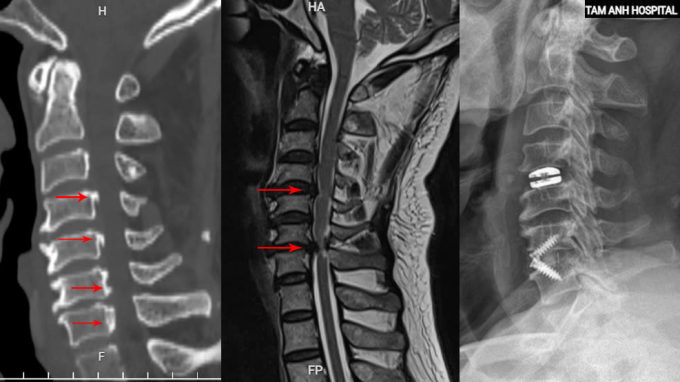

Tại Bệnh viện Đa khoa Tâm Anh Hà Nội, kết quả chụp cắt lớp vi tính (CT) cho thấy ông bị vôi hóa nhiều đoạn dây chằng dọc sau. ThS.BS Tạ Ngọc Hà, từ khoa Chấn thương Chỉnh hình, giải thích rằng lớp dây chằng này, vốn có vai trò quan trọng trong việc giữ vững cột sống, đã bị canxi hóa và dày lên, gây hẹp ống sống từ đốt sống cổ C3 đến C7. Kết quả chụp cộng hưởng từ (MRI) cũng cho thấy đĩa đệm C4-5 bị thoát vị và C6-7 thoát vị nặng, chèn ép tủy cổ nghiêm trọng.

Phương án phẫu thuật được lựa chọn là tối ưu và an toàn nhất cho bệnh nhân, theo đó bác sĩ sẽ mổ lối trước, bộc lộ mặt trước thân đốt sống, thay đĩa đệm nhân tạo C4-5 và cố định đốt sống C6-7. Bác sĩ Hà cho biết phương pháp này giúp bệnh nhân bảo tồn vận động cổ sau phẫu thuật.

Trong suốt ca phẫu thuật kéo dài 4 tiếng, bác sĩ Hà cùng êkíp đã sử dụng kính vi phẫu để bóc tách và giải phóng vùng tủy bị chèn ép. Khối thoát vị C4-5 được loại bỏ và thay thế bằng đĩa đệm nhân tạo. Đối với tổn thương đốt sống C6-7 nghiêm trọng hơn, bác sĩ Hà đã loại bỏ đĩa đệm và phần thoát vị chèn ép, giải phóng thần kinh, sau đó ghép xương nhân tạo và cố định lại bằng miếng ghép đĩa đệm có nẹp vít để tạo độ vững chắc cho toàn bộ cột sống cổ.